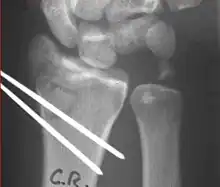

The techniques of surgical management include open reduction internal fixation (ORIF), external fixation, percutaneous pinning, or some combination of the above. The choice of operative treatment is often determined by the type of fracture, which can be categorized broadly into three groups: partial articular fractures, displaced articular fractures, and metaphyseal unstable extra- or minimal articular fractures.[4]

Surgical options have been shown to be successful in patients with unstable extra-articular or minimal articular distal radius fractures. These options include percutaneous pinning, external fixation, and ORIF using plating. Patients with low functional demand of their wrists can be treated successfully with nonsurgical management; however, in more active and fit patients with fractures that are reducible by closed means, nonbridging external fixation is preferred, as it has less serious complications when compared to other surgical options.[4] The most common complication associated with nonbridging external fixation is pin tract infection, which can be managed with antibiotics and frequent dressing changes, and rarely results in reoperation.[4] The external fixator is placed for 5 to 6 weeks and can be removed in an outpatient setting.[4]

These fractures, although less common, often require surgery in active, healthy patients to address displacement of both the joint and the metaphysis. The two mainstays of treatment are bridging external fixation or ORIF. If reduction can be achieved by closed/percutaneous reduction, then open reduction can generally be avoided. Percutaneous pinning is preferred to plating due to similar clinical and radiological outcomes, as well as lower costs, when compared to plating, despite increased risk of superficial infections.[21] Level of joint restoration, as opposed to surgical technique, has been found to be a better indicator of functional outcomes.[4]